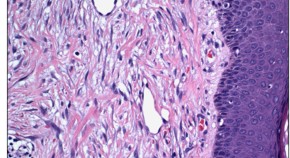

A growing body of evidence suggests that the mechanical functions of cardiac fibroblasts are an active and necessary component of myocardial growth and homeostasis. In this Review, Van Linthout and colleagues describe cell mechanosensation as a regulator of cardiac maturation and disease, and summarize the evidence showing that remodelling of the cardiac extracellular matrix, as a result of disease, can induce changes in the mechanical properties of the myocardium.